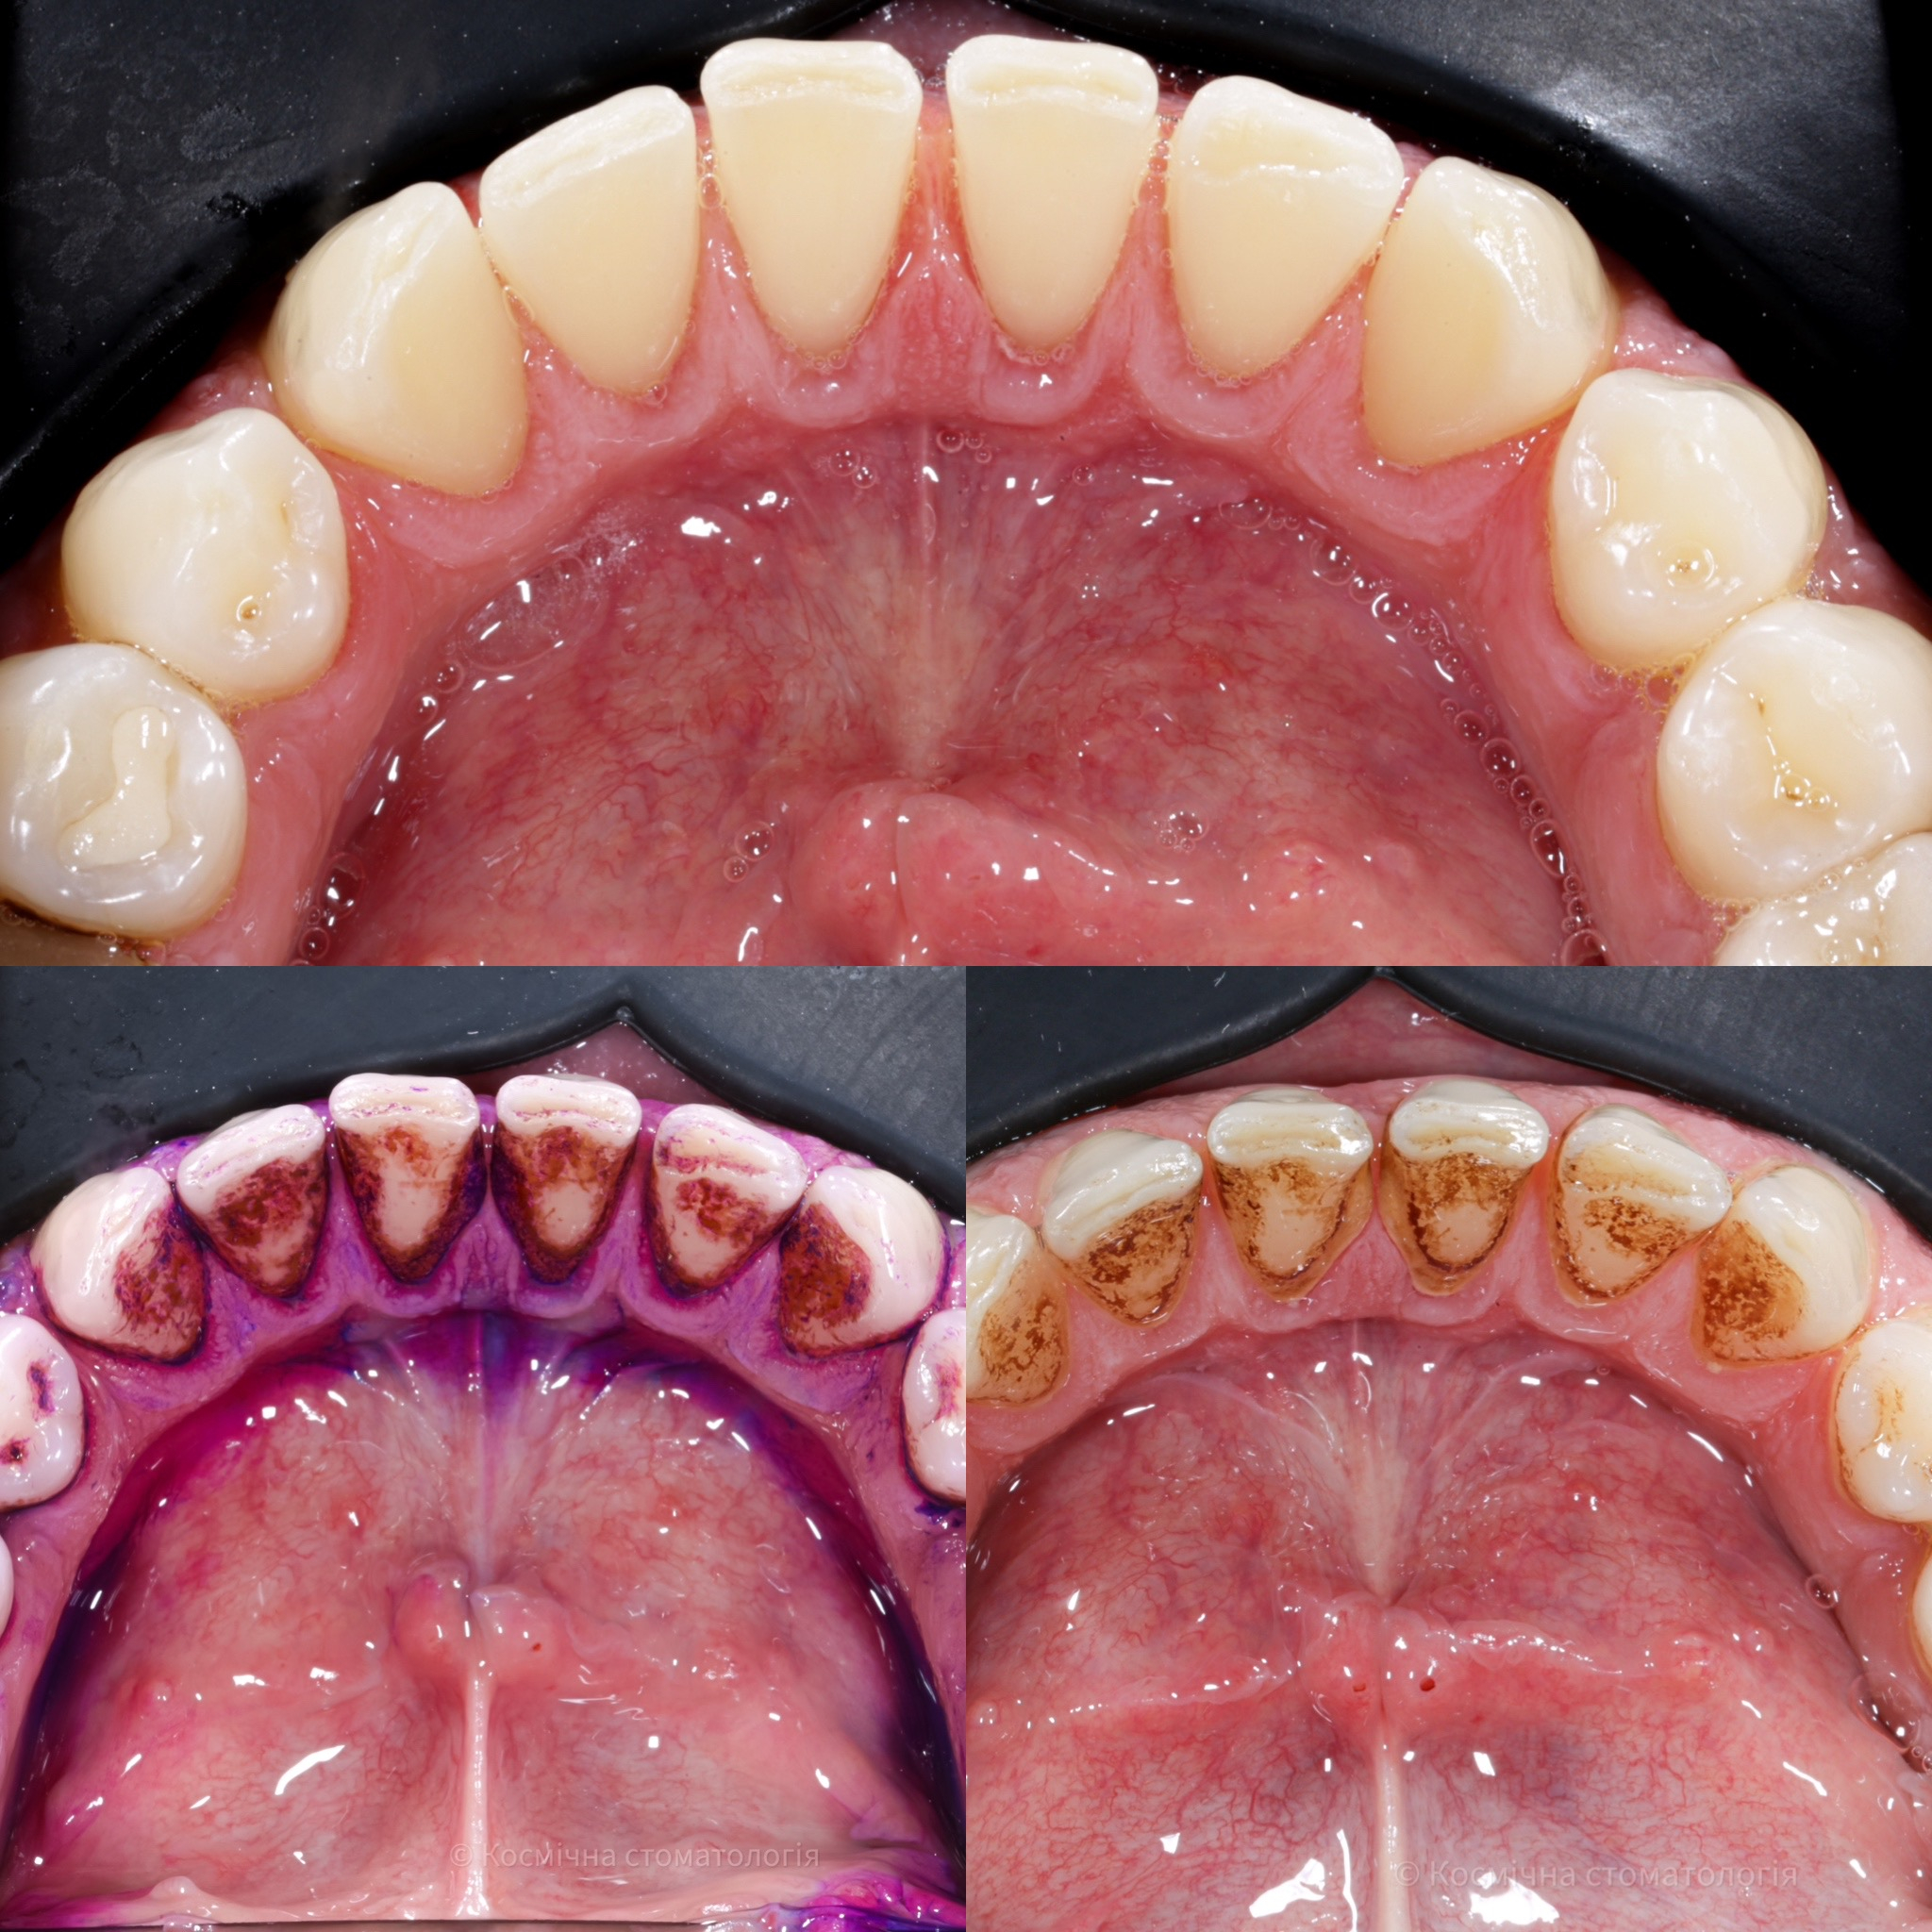

Галерея

Професійна гігієна (чистка) зубів складається з кількох етапів

• Комп'ютерна анестезія у разі підвищеної чутливості зубів.

• Зняття каменю ультразвуковим девайсом SIRONA (Німеччина) та звуковим наконечником KAVO (Німеччина) з електронним регулюванням потужності.

• Зняття каменю у важкодоступних місцях пародонтальними кюретами HU-Friedy.

• Зняття нальоту гігієнічними перлинами KaVo PROPHY pearls SUPRAGINGIVAL CALCIUM CARBONATE в індивідуальних пакуваннях із ароматом на вибір: персик, апельсин, м'ята, чорна смородина та нейтральний смак.

• Полірування швейцарською пастою Proxyt Ivoclar Vivadent для блиску та природної білизни.

• Діагностика прихованих захворювань ясен (скрінінг-тест).

• Покриття зубів фтористим лаком у місцях підвищеної чутливості;

• Ремінералізуюча терапія;

Ультразвукова чистка зубів

Зубний камінь, в залежності від місця утворення, поділяється на над- та підясенний. Найбільшу небезпеку для здоров'я зубів становить другий тип, адже це дуже сприятливе середовище для шкідливих бактерій.

При проведенні професійної гігієни застосувується ультразвуковий скалер, що дозволяе видалити зубний камінь разом з хвороботворними бактеріями з підясенних кишень.

Повітряно-абразивна чистка зубів (Air Flow)

Завдяки піскоструменевому апарату з технологією Air Flow, який використовуючи тиск повітря та води, подає на зубну емаль спеціальний абразивний склад, зуби можна очистити не лише від м’якого нальоту, а й від пігменту. Для видалення нальоту, в Космічній стоматології Драганчука ми використовуємо KaVo prophy pearls supragingival calcium carbonateneutral.

Чистка зубів щіточками та пастами

Фінальний етап професійної гігієни - полірування спеціальними щіточками та пастою, щоб усунути мікротріщини та шорохуватості, що виникли після чистки та видалити залишки нальоту, що могли в них залишитись. Це дозволяє суттєво уповільнити формування нових відкладень.

Полірування зубної емалі гумками

Кінцеве полірування поверхні зубів проводиться із застосуванням різних насадок, зокрема спеціальних гумок, що надає зубам ідеальної гладкості та блиску. Спеціальні гумові насадки відмінно справляться з наданням естетичної довершеності твоїй посмішці.